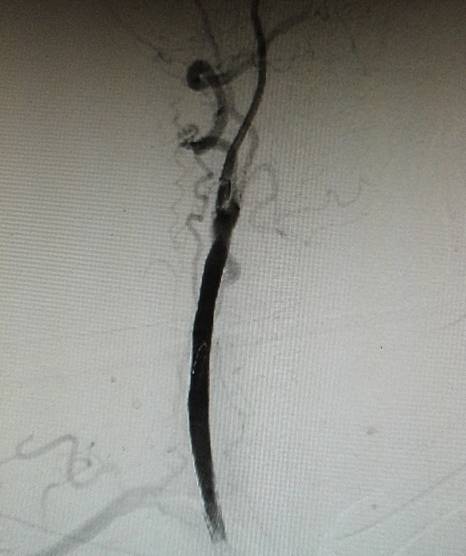

经动脉鞘造影,可见颈总动脉通畅,但管腔狭窄,不规则。

然后球囊扩张,植入颈总动脉支架,造影示,右侧颈总动脉显影好。

此次分享两例颈动脉闭塞复合手术开通病例。第一例为颈内动脉长段闭塞,从颈内动脉起始段开始闭塞。患者术前存在眼动脉缺血事件及右侧半球灌注不足。颈内动脉剥脱后,颈内动脉可淡淡显影,为微导管通过创造条件。微导管通过后,顺利完成球囊扩张及支架植入,完全开通右侧颈内动脉。第二例为右侧颈总动脉闭塞患者,虽有颈外动脉代偿,但仍存在TIA及右侧大脑半球灌注不足。经颈动脉内膜剥脱后,造影可见颈总动脉显影,但管腔严重不规则,经球囊扩张及支架植入后,颈总动脉显影好。两例患者术后7天复查颈动脉CTA,均显示颈内动脉起始处较术后造影增粗。